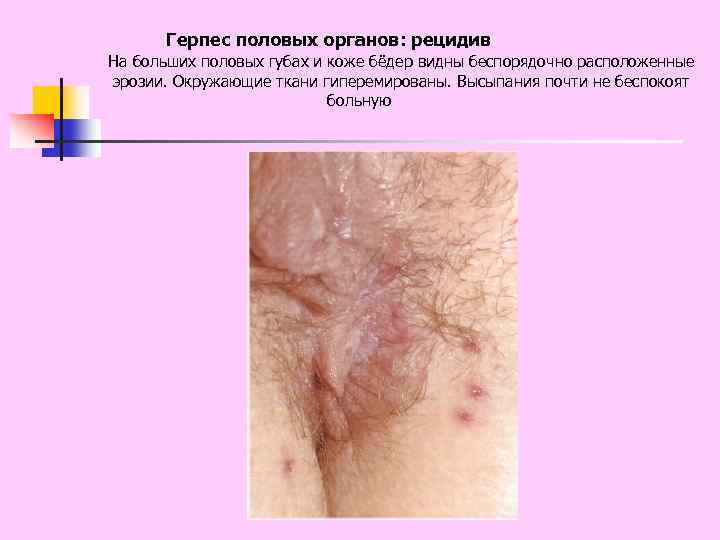

Герпес половых органов: рецидив На больших половых губах и коже бёдер видны беспорядочно расположенные эрозии. Окружающие ткани гиперемированы. Высыпания почти не беспокоят больную

Герпес половых органов: рецидив На больших половых губах и коже бёдер видны беспорядочно расположенные эрозии. Окружающие ткани гиперемированы. Высыпания почти не беспокоят больную